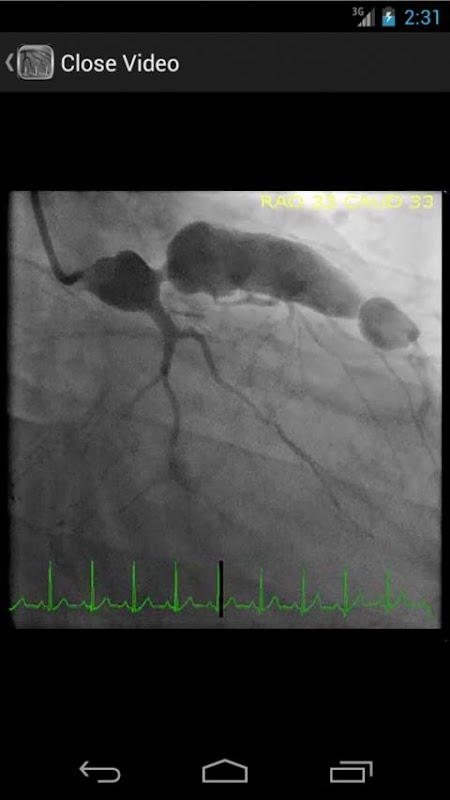

* Database Dicari mengandung lebih dari 30 video (angiogram koroner, ventriculograms, dan aortograms) dari kedua temuan umum dan langka di laboratorium kateterisasi jantung